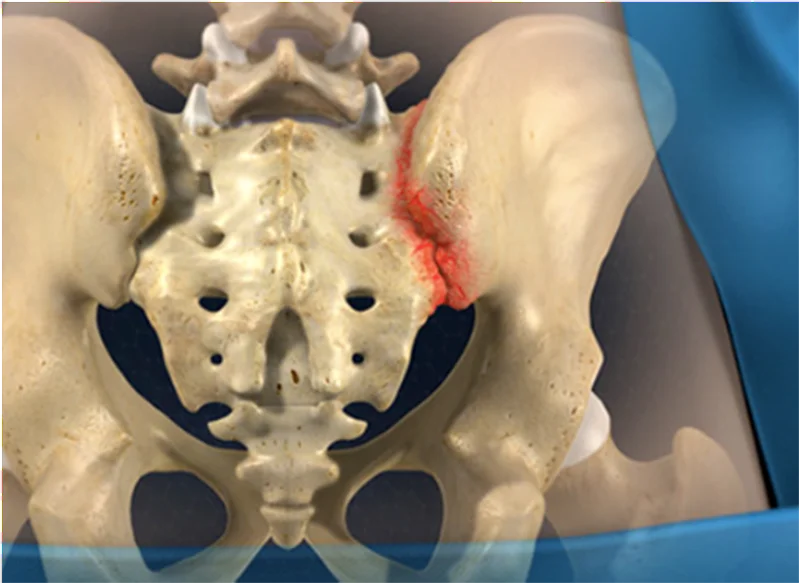

Крижово-клубові суглоби підтримують хребет і витримують вагу тіла. Вони підтримуються міцними зв’язками, що проходять навколо задньої частини таза. Сідничні та грушоподібні м’язи також допомагають зміцнити суглоб. МРТ може виявити запалення, яке може бути невидимим за допомогою інших методів візуалізації, таких як КТ та рентген.

Крижово-клубовий суглоб з’єднує нижню частину спини з тазом і утворюється клубовою кісткою та крижовою кісткою (2 кістки, які утворюють частину тазу). Є два крижово-клубових суглоби - один зліва і один з правого боку. Біль у крижово-клубовому суглобі вражає як чоловіків, так і жінок будь-якого віку, але найчастіше спостерігається у активних жінок у віці 20-40 років. Також часто зустрічається у людей, які займаються спортом, і у вагітних жінок.

- Травма – біль у крижово-клубовому суглобі може бути спричинений падінням, наприклад падінням з коня, під час катання на лижах, зі сходів, тобто «пропущеним кроком».